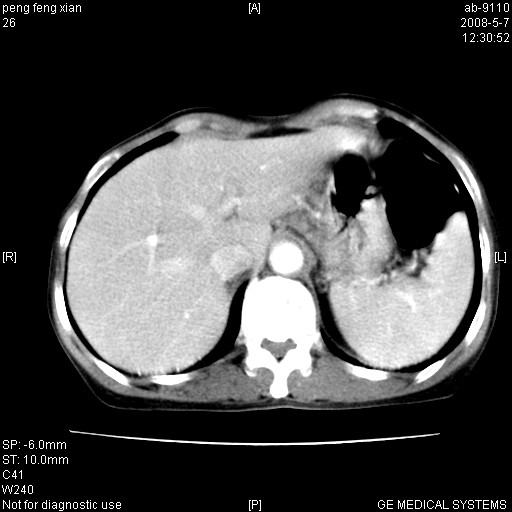

女,56岁。b超左一腹包块,考虑胃肠道肿瘤。

胃壁增厚,左前胸壁局限性隆起,考虑胃癌可能性大,建议做胃镜

典型胃癌胰体尾部受侵。

胃体部胃壁增厚,不均匀性强化,与胰腺分解欠情.

考虑:胃癌,胰腺受侵待除外.

鉴别:胃淋巴瘤(强化不明显)

建议:胃镜检查.